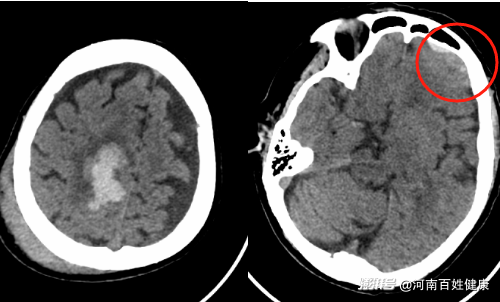

入院后立即完善CT等相關(guān)檢查,出血較少暫無手術(shù)指征,需密切觀察體征變化,最終以“硬膜下血腫”收至住院,對癥治療。

復(fù)查CT提示:右側(cè)額頂葉腦出血較前范圍增大;左側(cè)額葉腦出血較前新增;左側(cè)額部硬膜下血腫較前明顯增多,此時劉奶奶已出現(xiàn)嗜睡癥狀,情況危急需立即手術(shù)治療。